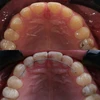

Diş Çapraşıklığı

Implant tedavisi